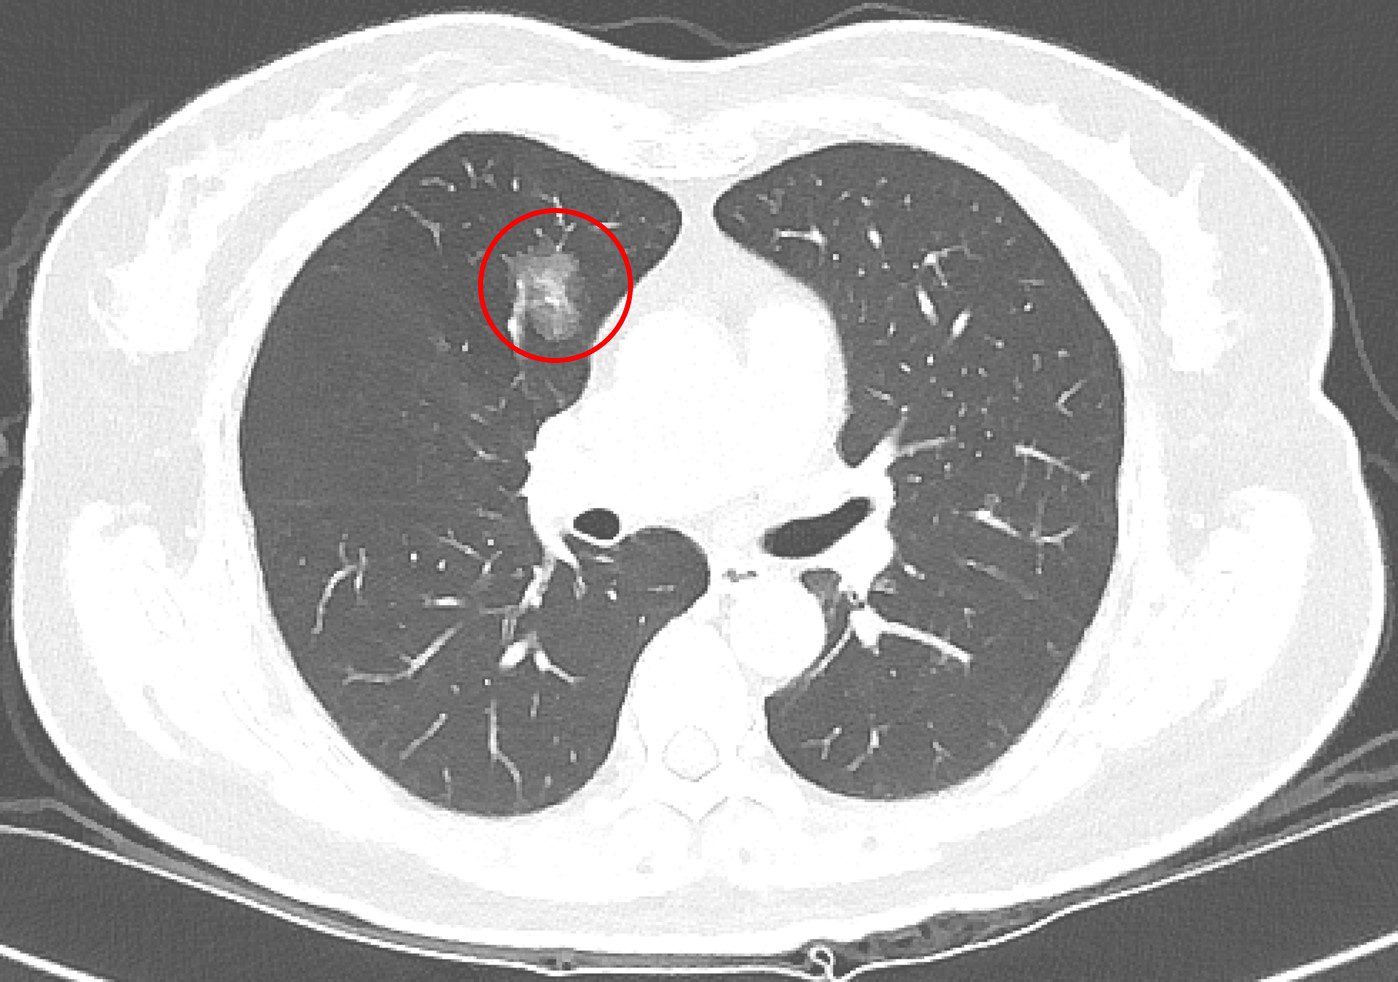

肺癌發生率已居全國第一,影響因子包括抽菸、肺癌家族史及空氣污染等,但吳智偉醫師指出,臨床上超過一半肺癌患者其實不抽菸,因此即使沒有抽菸習慣,也不能完全輕忽風險。近年政府積極推動低劑量電腦斷層篩檢,提升肺癌早期發現及治療的機會,針對肺部小結節,臨床上雖會依據大小、影像型態、生長狀況以及病人的臨床背景進行綜合判斷,但部分良性病灶在影像上與早期肺癌相似,有些早期惡性病灶則生長緩慢、不易立即判別。

有鑑於篩檢發現的小型肺結節在診斷與後續處置上仍有不少挑戰,吳智偉醫師回溯分析台北慈濟醫院2013年至2018年間共6997名LDCT篩檢者資料,並追蹤至2023年,探討篩檢發現之肺腫瘤的生長模式、病理診斷、診斷時程及電腦斷層導引切片的準確性。研究結果顯示,接受手術或切片的腫瘤中,約有三分之二為惡性腫瘤,並以肺腺癌最為常見;而其餘三分之一的良性病理發現則是以纖維化和炭粒沉積最常見。吳智偉醫師說明,纖維化通常是肺部過去曾受感染或發炎後留下的疤痕,炭粒沉積則是空氣中的污染微粒被吸入肺部後堆積形成的結節。這兩類良性病灶之所以難以分辨,在於影像上與早期肺癌相似,因此即使經過多重評估,目前的醫學仍難以僅憑影像,準確區分良性或惡性。此外,約有13%的良性腫瘤,在追蹤的過程中以新發生的病灶(de novo)的形式被發現,讓影像的初期判斷更加艱難。

極早期的結節因為太小,無法經由穿刺切片確認屬性。吳智偉醫師提醒,發現肺結節不必過度恐慌,也不代表一定要立刻動刀,目前國內外的共識是以大小0.8公分作為最基礎的判斷準則,在困難判讀的情況下,建議須定期追蹤。若在追蹤期間出現變大或影像特徵改變,建議與醫師討論或進一步評估手術時機,通常會有機會在零期或第一期及早治療。肺癌若能早期發現,五年存活率超過九成,因此民眾若檢查發現肺結節,應依醫囑規律回診追蹤,才是保護肺部健康的關鍵。